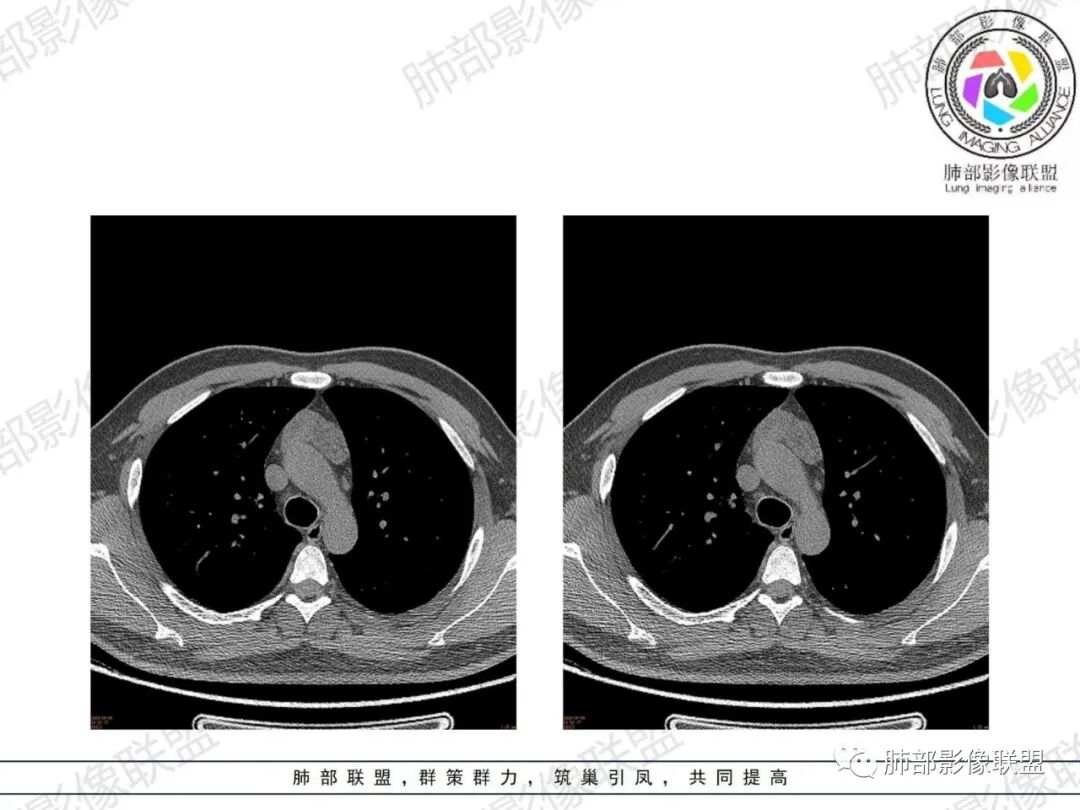

胸腺增生CT表现

体积、形态:

弥漫性增大,两缘对称,质地柔软,部分淋巴性胸腺增生的大小正常;形态保持其正常形态,呈类圆形、梨形,边缘光滑,可呈浅分叶

密度:

密度均匀,呈肌性密度,偶见细小钙化,其内有脂肪浸润样密度影

强化:

轻度或无强化

与周围结构关系:

与周围大血管、胸骨等周围组织结构分界清楚,无淋巴结肿大、胸膜及心包受累。

1、年轻男性,双下肌乏力,胸部CT提示前纵隔胸腺区病变,应当怀疑胸腺增生或胸腺瘤导致的重症肌无力。

2、前纵隔梨形软组织密度影,与正常胸腺形态一致,为胸腺弥漫性增大,两缘匀称,质地柔软,未见明显膨隆,其内可见脂肪浸润影,与周围结构分界清楚,再加上病人年龄,需要高度提示胸腺增生(淋巴滤泡样增生型)。胸腺瘤一般无脂肪浸润,质地较硬,呈结节或肿块状,且发病年龄较大。B2B3型肿块边界不清,可侵犯临近组织脏器,B3可胸膜转移,胸腺癌可引起纵隔淋巴结及远处转移。